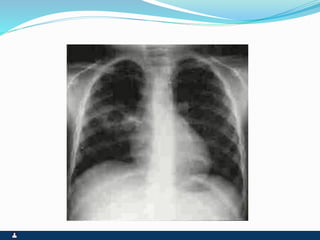

ATELECTASIA

OBSTRUÇÃO BRÔNQUICA SINAIS ATELECTASIA ENFISEMALOCALIZADO  OBSTRUÇÃO BRONQUICA COMPLETA  RETRAÇÃO TORÁCICA OU INTERCOSTAL  DESVIO HOMOLATERAL DO MEDIASTINO ( TRAQUÉIA)  EXPANSIBILIDADE REDUZIDA  FTV AUSENTE  MACICEZ LOCALIZADA  MV AUSENTE  RONCOS OU SIBILOS LOCALIZADOS  ATRITO PLEURAL EVENTUAL  OBSTRUÇÃO BRÔNQUICA INCOMPLETA, COM MECANISMO VALVULAR  ABAULAMENTO TORÁCICO OU INTERCOSTAL  DESVIO CONTRA LATERAL DO MEDIASTINO ( TRAQUÉIA )  EXPANSIBILIDADE REDUZIDA  FTV REDUZIDO OU AUSENTE  HIPERSONORIDADE LOCALIZADA  MV REDUZIDO OU AUSENTE  RONCOS OU SIBILOS LOCALIZADOS  ESTERTORES BRÔNQUICOS OU ALVEOLARES EVENTUAIS